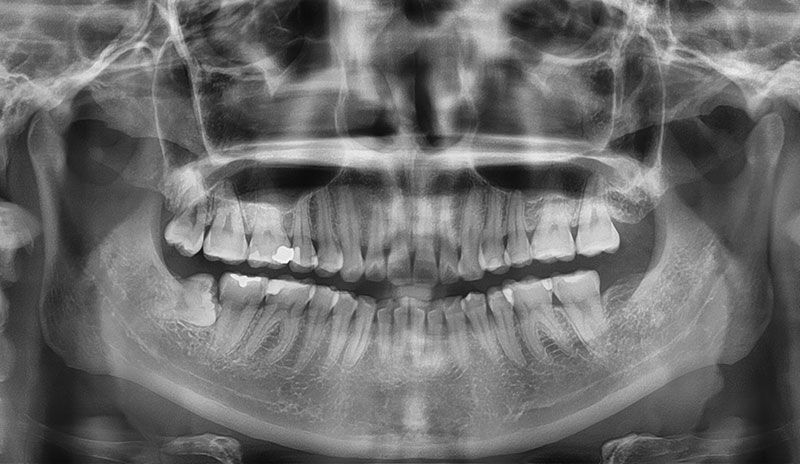

阻生智齒很常見,因為智齒要萌發時,牙弓位置不足,導致卡在骨頭內,沒有空間往上長出來。

常常呈現卡在第二大臼齒後長不出來的情況,或是牙齒根部呈現完全水平的姿態,因為清潔不易,所以容易導致牙齦發炎,甚至蛀牙,這樣的智齒通常建議拔除。